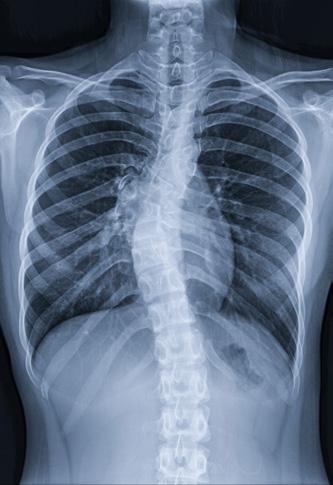

Consecințele scoliozei asupra respirației și calității somnului

colioza congenitală este prezentă la naștere și rezultă din malformații vertebrale sau costale, adesea asociate cu tulburări sistemice. Pe de altă parte, scolioza idiopatică, care constituie aproximativ 85% din cazuri, nu are o cauză specifică identificată și apare în perioadele de creștere rapidă. Scolioza asociată cu sindroame cunoscute este adesea subclasificată drept „scolioză sindromică”. Un aspect esențial în evaluarea scoliozei este măsurarea unghiului Cobb, un indicator obiectiv al severității deformării. Acest unghi, format prin intersectarea liniilor trasate perpendicular pe vertebrele de la extremitățile curbei, este direct proporțional cu severitatea scoliozei. Studiile clinice arată că anomaliile funcției pulmonare devin detectabile la un unghi Cobb între 50 și 60 de grade. În cazurile severe, cu un unghi Cobb de peste 90 de grade, riscul de insuficiență cardiorespiratorie este semnificativ crescut.

Modificările structurale cauzate de scolioză au un impact direct asupra mecanicii respiratorii. Deformarea coloanei vertebrale și a toracelui reduce complianța peretelui toracic, limitează mobilitatea coastelor și afectează forța musculaturii intercostale. Aceste schimbări conduc la o scădere a volumului pulmonar și deter-

mină compresia focală a căilor respiratorii. În special la copiii cu scolioză cu debut precoce, limitarea creșterii normale a toracelui și a plămânilor poate avea consecințe pe termen lung asupra dezvoltării respiratorii.

În practica clinică, pacienții cu scolioză pot dezvolta un tipar de respirație rapidă şi superficială, în încercarea de a compensa rigiditatea peretelui toracic. Această adaptare conduce la o scădere a capacității de efort şi la apariția dispneei de efort, una dintre primele manifestări clinice ale scoliozei. Implicarea coloanei toracice (singură sau în combinație cu segmentul lombar) în scolioză este responsabilă pentru complicațiile respiratorii şi cardiovasculare, iar distorsiunea cutiei toracice creşte efortul respirator necesar.

Deși scolioza nu afectează direct mușchii respiratori, aceasta poate restricționa funcționarea lor. De exemplu, mușchii intercostali pot deveni „supraîntinși” sau pot avea dificultăți în a se extinde din cauza modificărilor dintre spațiile intercostale, ceea ce le reduce eficiența, inclusiv capacitatea de expansiune a toracelui. Deformarea cutiei toracice determină un perete toracic (și, implicit, un sistem respirator) mult mai puțin elastic, ceea ce crește efortul necesar pentru respirație. Datorită interconexiunilor complexe dintre coloana vertebrală, stern și coaste, mișcarea și rotația vertebrelor în cazul

Figura 1 Scolioza

scoliozei au un impact semnificativ asupra formei toracelui, generând o latură convexă și una concavă. Pe lângă severitatea curbei coloanei vertebrale, vârsta pacientului joacă un rol în distribuția inegală a gazelor alveolare. Reducerea capacității de a efectua efort fizic la copiii cu scolioză nu se datorează doar scăderii capacității respiratorii, ci și diminuării abilității inimii de a se adapta la cerințele metabolice crescute. De asemenea, micșorarea diametrului anteroposterior al toracelui la acești copii determină o deplasare a inimii, afectând astfel funcționarea acesteia.

Un alt aspect important al conexiunii dintre scolioză și afectarea respiratorie este influența scoliozei asupra somnului. Studiile arată că pacienții cu scolioză, în special cei cu debut precoce, prezintă frecvent tulburări respiratorii în timpul somnului, cum ar fi hipopneea și apneea. Aceste tulburări sunt mai pronunțate în timpul somnului REM și sunt asociate cu scăderea saturației de oxigen.

Hipoventilația în timpul somnului cu creșterea concentrației de dioxid de carbon se poate manifesta cu următoarele simptome: cefalee matinală, somnolență/oboseală în timpul zilei, iritabilitate, somn agitat, coșmaruri, transpirații nocturne, scădere în greutate, infecții respiratorii frecvente, dispnee.

Cu toate acestea, studiile au evidențiat că la copiii cu scolioză cu debut precoce hipoventilația alveolară se manifestă inițial pe timpul nopții iar simptomele respiratorii pot fi absente. Acest lucru nu exclude afectarea respiratorie, motiv pentru care

evaluarea periodică și precoce a funcției respiratorii este esențială pentru a surprinde evoluția spre insuficiență respiratorie. Evaluarea funcției respiratorii la acești pacienți include metode non-invazive precum: